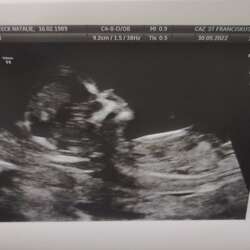

Bij mijn vorige zwangerschap heb ik op 6 weken ook een bloeding gehad .. ( na deze bloeding nog 2x in de weken nadien trouwens ) ik ben toen onmiddelijk mogen langs gaan voor een echo ( België) .. op de echo zagen ze toen steeds een vlek bloed zitten in de baarmoeder naast het vruchtzakje .. wat het betekende hebben ze me nooit echt duidelijk uitgelegt .. wel dat ik toen rustig aan moest doen , medicatie nemen ( om op te steken in de vagina) en afwachten ..